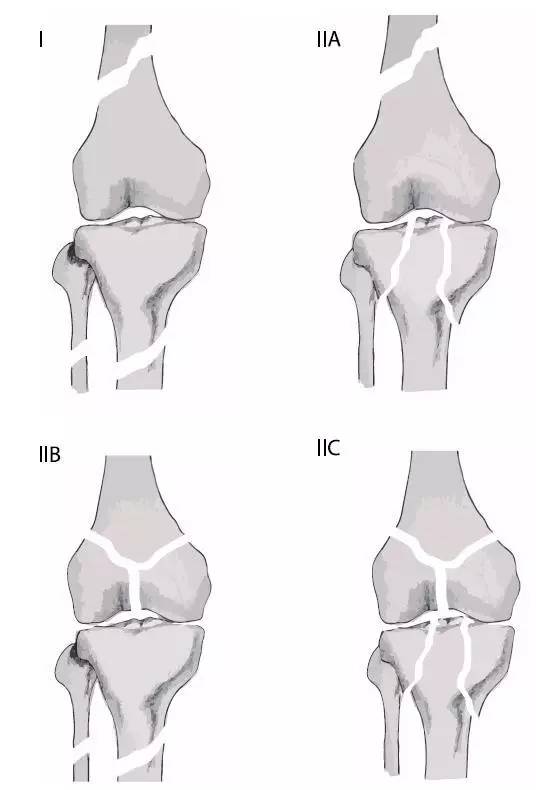

浮膝的 Fraser's 分型(来源:Management of the Floating Knee in Polytrauma Patients. Open Orthop J. 2015 Jul 31;9:347-55.)